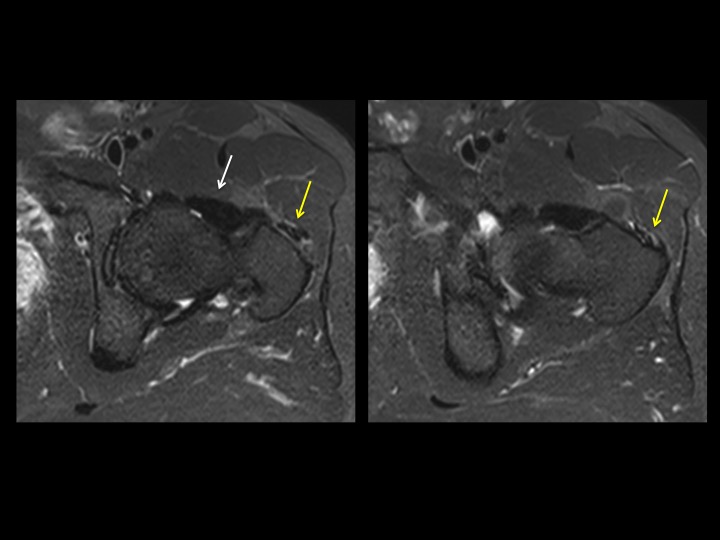

42M chronic pain with reported work injury 17 months ago

There is marked dark signal capsular thickening anteriorly and superiorly (white arrows). The reference, based on arthrography, refers to much thinner capsular measurements, and does not specify where measurements are made (these are mid superior and anterior). Is this chronic adhesive capsulitis? There is also insertional G Minimus tendinosis (yellow arrows) and degenerative tearing of the anterior labrum. The patient specified that pain is worst posteriorly. Last image from a different patient today with comparatively normal appearing capsule. Reference article.